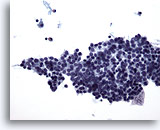

Figure 75

Lymph node FNA, Hodgkin’s disease.

A cellular specimen is pictured with the vast majority of cells being small round lymphocytes, but with two large bizarre cells that at this magnification are consistent with Reed-Sternberg cells. 20x

Lymph node FNA, Hodgkin’s disease.

A cellular specimen is pictured with the vast majority of cells being small round lymphocytes, but with two large bizarre cells that at this magnification are consistent with Reed-Sternberg cells.

20x